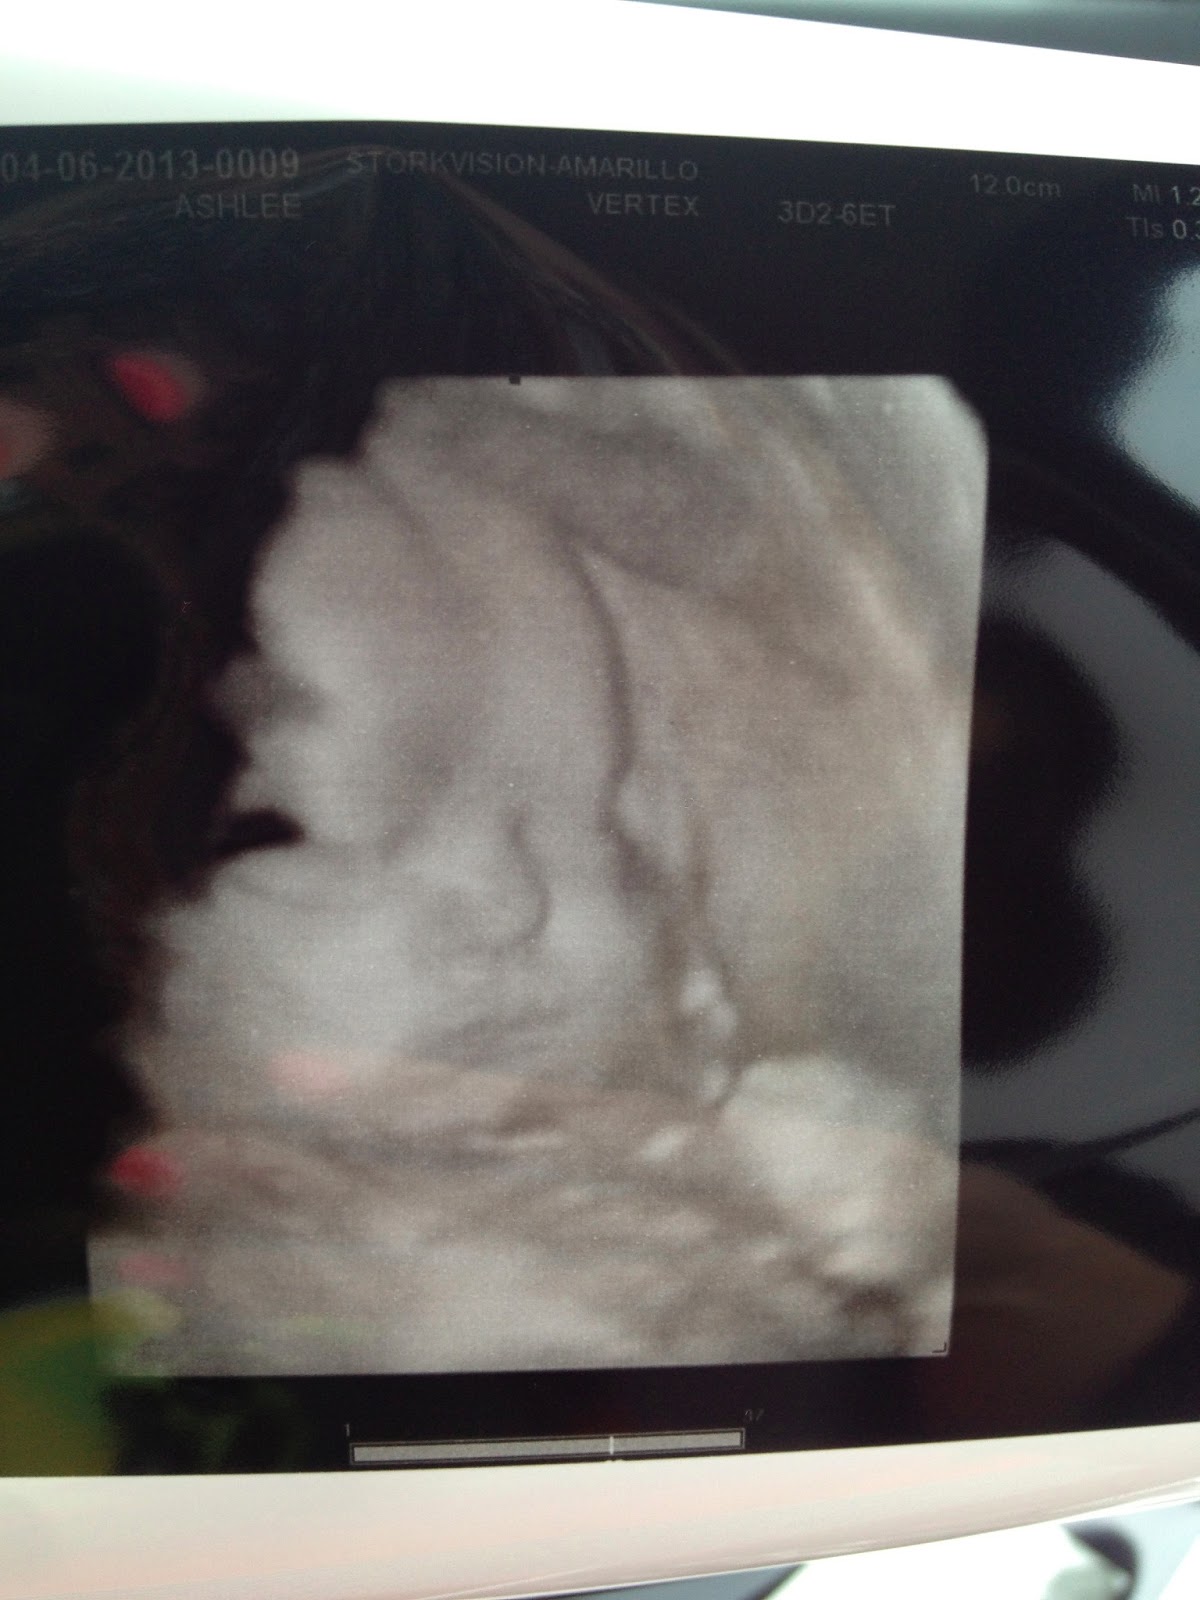

- Best Moment of the Week: Seeing Little Miss in a 3d/4d sonogram, getting her bedding in…and I LOVE IT….and having our first shower given by my “school family”. It’s been a busy, fun and exhausting week! 🙂

Here are some pictures from the sonogram!30 weeks!